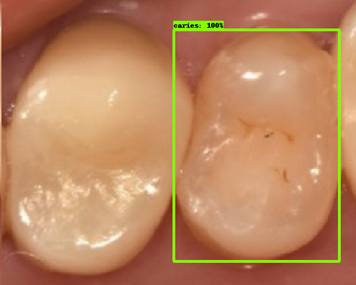

| 모델예측 | 정답 |

|---|---|

![]() |

- 인식이 잘 되지 않은 케이스들을 보면, 사람의 눈으로 뚜렷하게 충치로 판단되는 치아를 모델이 잡아내지 못하는 경우도 있었지만, 그보다는 사람의 눈으로도 충치로 분류하기 어려운 경우에 모델역시 잘 분류해내지 못하는 것을 볼 수 있었습니다. 예를 들어, 인식이 잘되지 않은 첫번째 케이스, 세번째 케이스를 보면 정답지에는 충치 치아로 분류되어 있지만, 사람이 한눈에 보기에도 충치라고 판단하기 어려운 사진들이었습니다. 이러한 경우에 모델은 잘 잡아내지 못하고 있습니다.